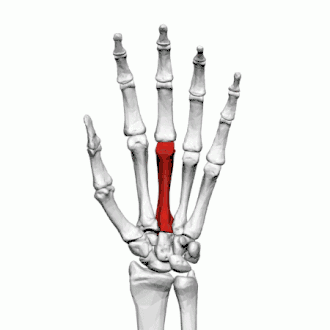

Troisième métacarpien

Description

Le troisième métacarpien est plus court que le deuxième métacarpien.

Base

Sur la face dorsale de sa base se présente sur son côté radial une éminence pyramidale : le processus styloïde du troisième os métacarpien, qui s'étend vers le haut en arrière du capitatum. Dans la partie supérieure se trouve une surface rugueuse pour l'insertion du muscle court extenseur radial du carpe.

La facette articulaire carpienne est concave en arrière, plate en avant et s'articule avec le capitatum.

Du côté radial se trouve une facette lisse et concave pour l'articulation avec le deuxième métacarpien, et du côté ulnaire deux petites facettes ovales pour le quatrième métacarpien.

Corps

La diaphyse donne naissance aux deuxième et troisième muscle interosseux dorsaux de la main.